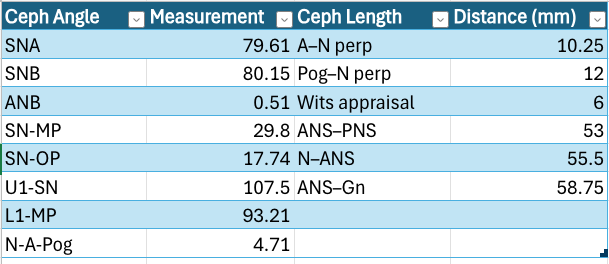

Either way, the following are my ceph measurements, the most important of which is the Wit's appraisal:

Wit's appraisal basically tells you exactly how many mm your jaws are misaligned. It's a good measurement as it bypasses compensation; my recession is a bit hidden due to previously having invisalign. Positive values on a Wit's are a recessed maxilla; negative values are a recessed mandible. As you can see, my maxilla is ~6mm recessed, (Class III Malocclusion) and when combined with a few of these other measurements (cross-referenced with ideals), I need my maxilla moved forward+ccw rotation.

My breathing is hella impacted by my maxilla's recession. The ANS-PNS measurement shows that my maxilla has a fully developed length, but the Wits appraisal still shows its recession. Due to this, it cuts off my airway. I at least have UARS, or Upper Airway Resistance Syndrome, if not full OSA, or Obstructive Sleep Apnea.

My breathing is hella impacted by my maxilla's recession. The ANS-PNS measurement shows that my maxilla has a fully developed length, but the Wits appraisal still shows its recession. Due to this, it cuts off my airway. I at least have UARS, or Upper Airway Resistance Syndrome, if not full OSA, or Obstructive Sleep Apnea.